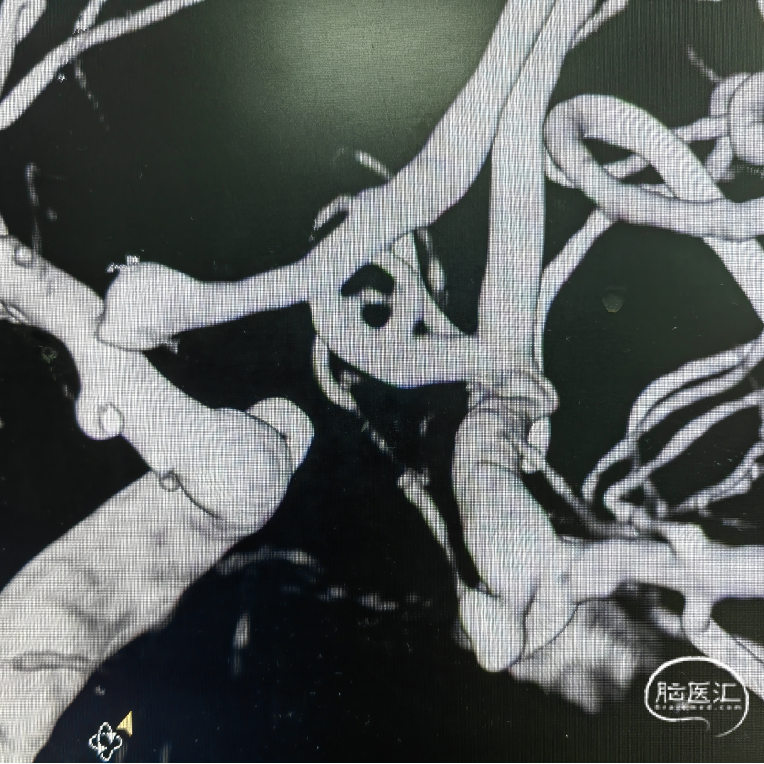

动脉瘤与载瘤动脉关系分析:

红色曲线(经同侧入路栓塞微导管需塑形形状,塑形困难)

蓝色曲线(经对侧入路栓塞微导管需塑形形状,塑形简单)